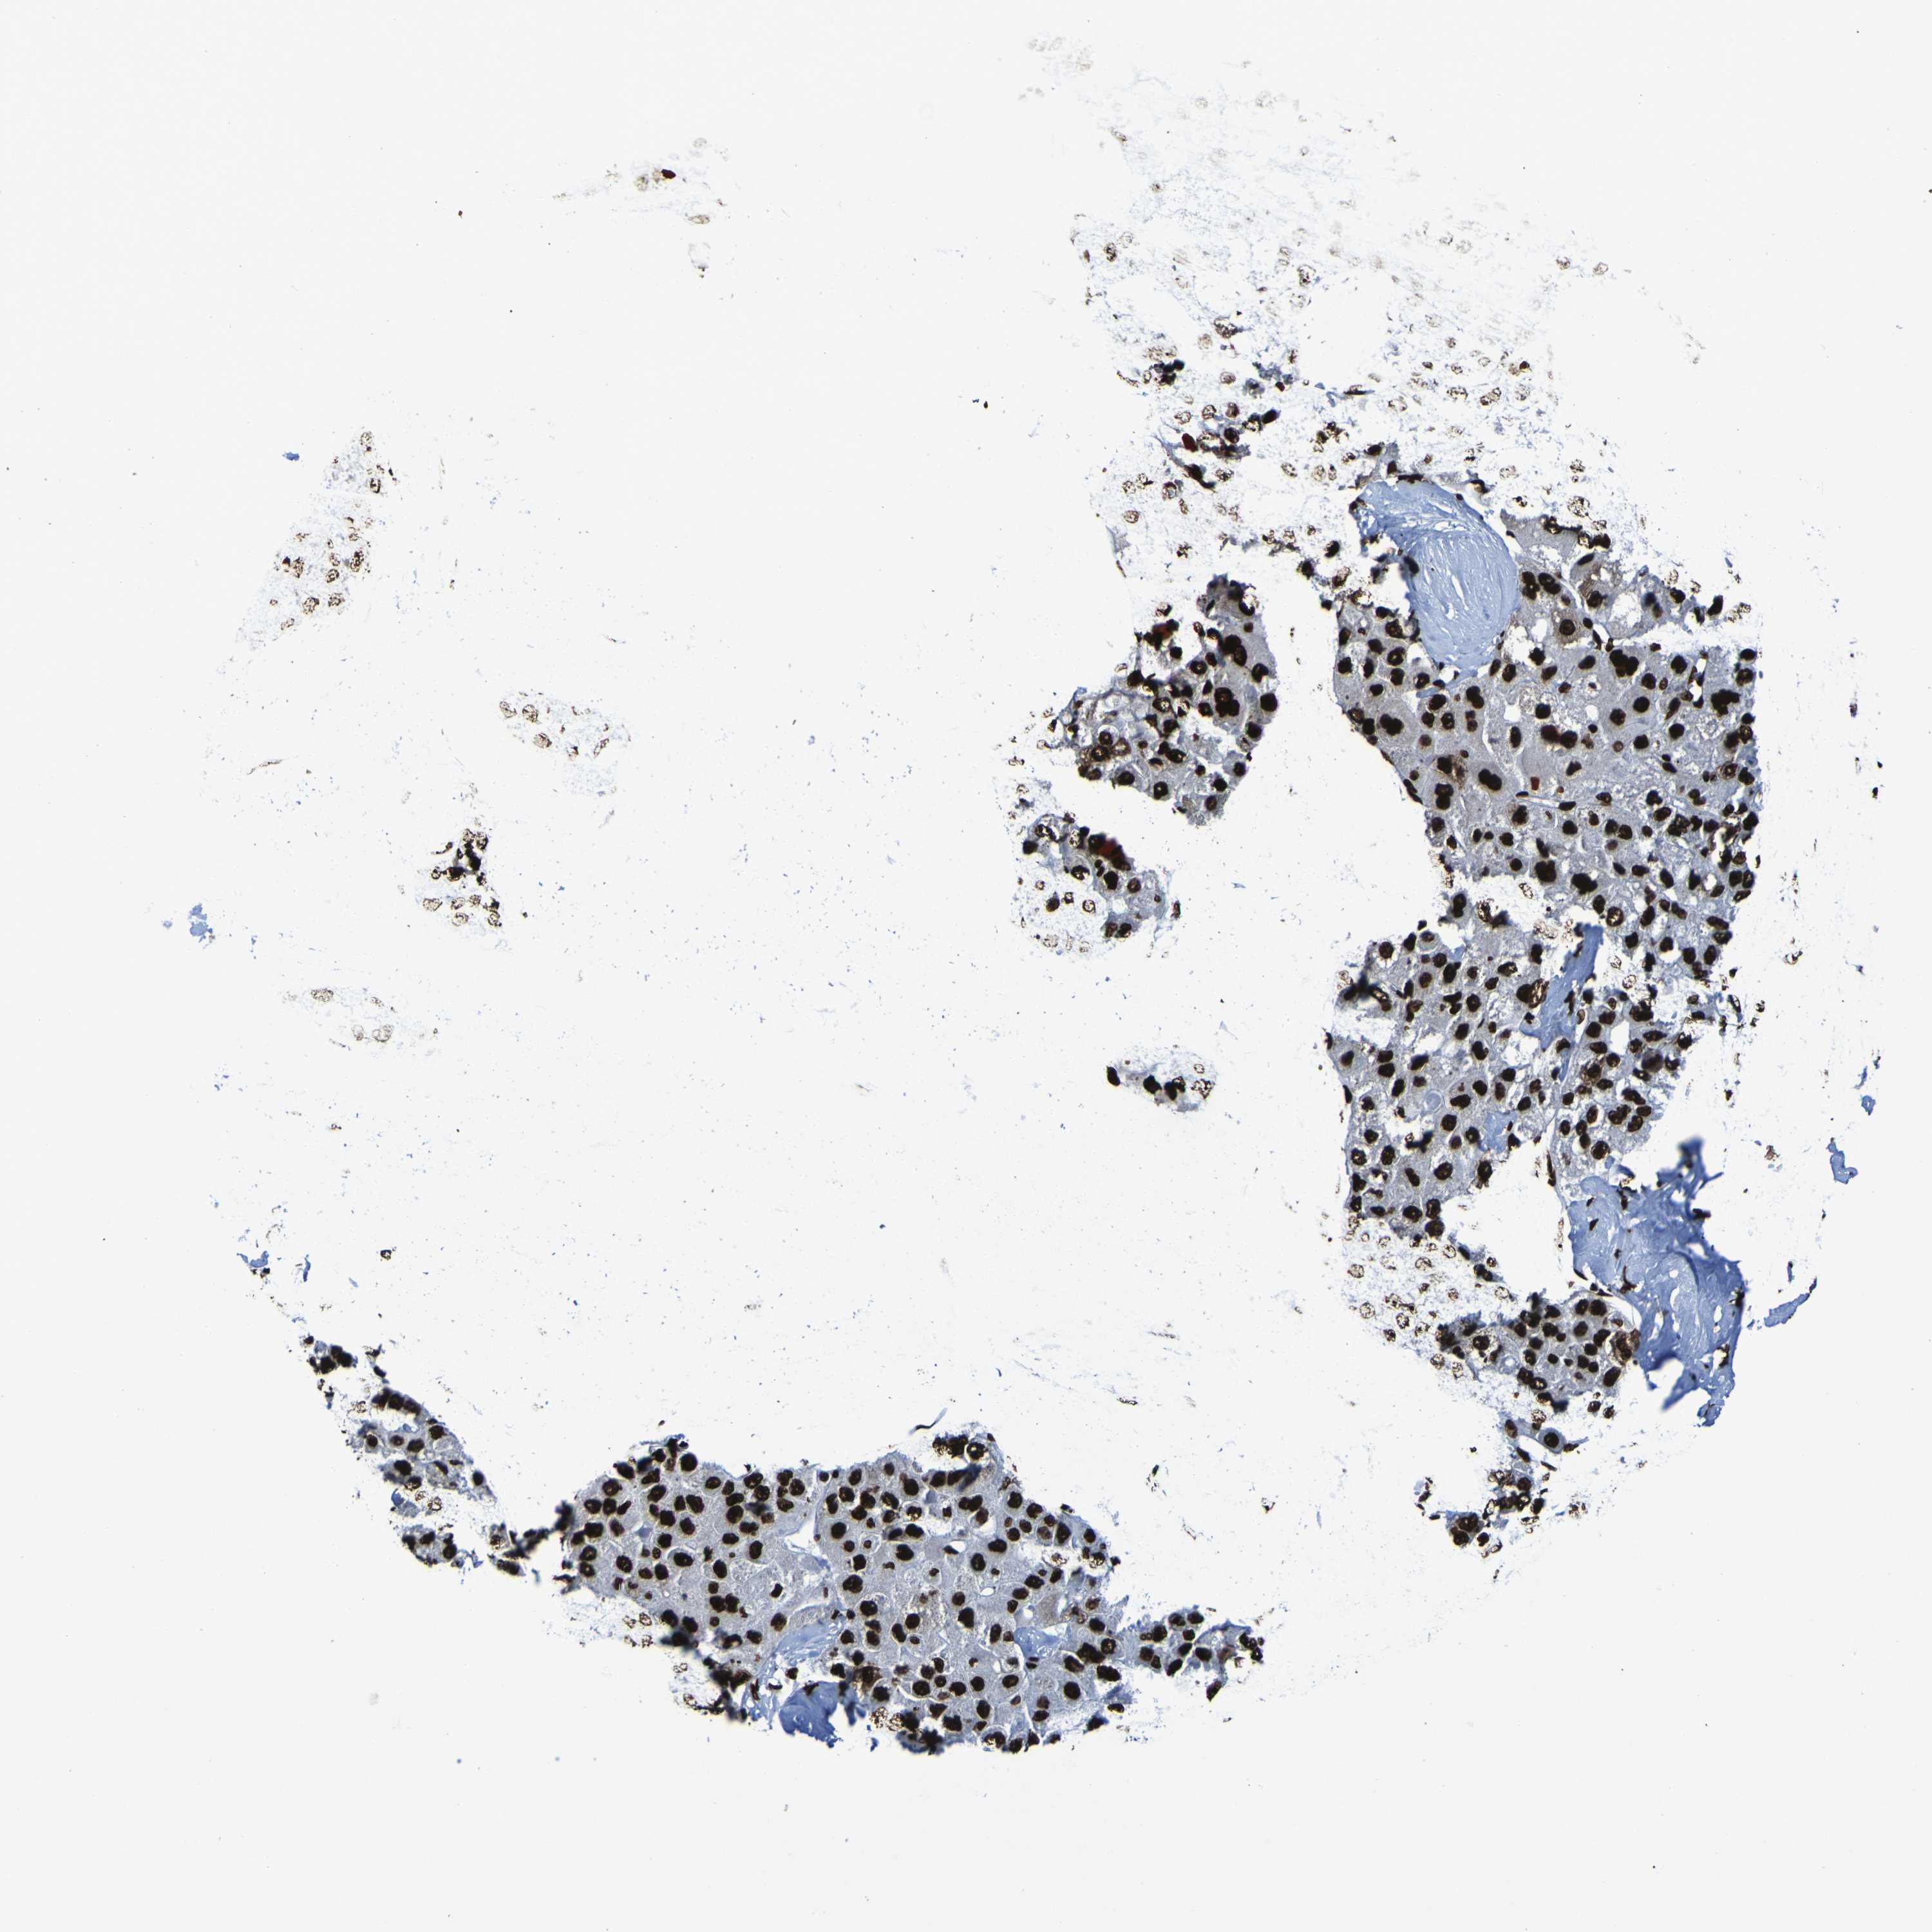

LIVER CANCER - Protein expressioni

A mouse-over function shows sample information and annotation data. Click on an image to view it in a full screen mode. Samples can be filtered based on level of antibody staining by selecting one or several of the following categories: high, medium, low and not detected. The assay and annotation is described here.

Note that samples used for immunohistochemistry by the Human Protein Atlas do not correspond to samples in the TCGA dataset.

Antibody stainingi

Antibody staining in the annotated cell types in the current human tissue is reported as not detected, low, medium, or high, based on conventional immunohistochemistry profiling in selected tissues. This score is based on the combination of the staining intensity and fraction of stained cells.

Each image is clickable and will lead to virtual microscopy that enables deeper exploration of all samples and also displays staining intensity scores, fraction scores and subcellular localization as well as patient and tissue information for each sample.

Antibody HPA011384

Antibody CAB012983

Staining

High

Medium

Low

Not detected

Intensity

Strong

Moderate

Weak

Negative

Quantity

>75%

75%-25%

<25%

None

Location

Nuclear

Cytoplasmic/membranous

Cytoplasmic/membranous,nuclear

Cholangiocarcinoma

Carcinoma, Hepatocellular, NOS